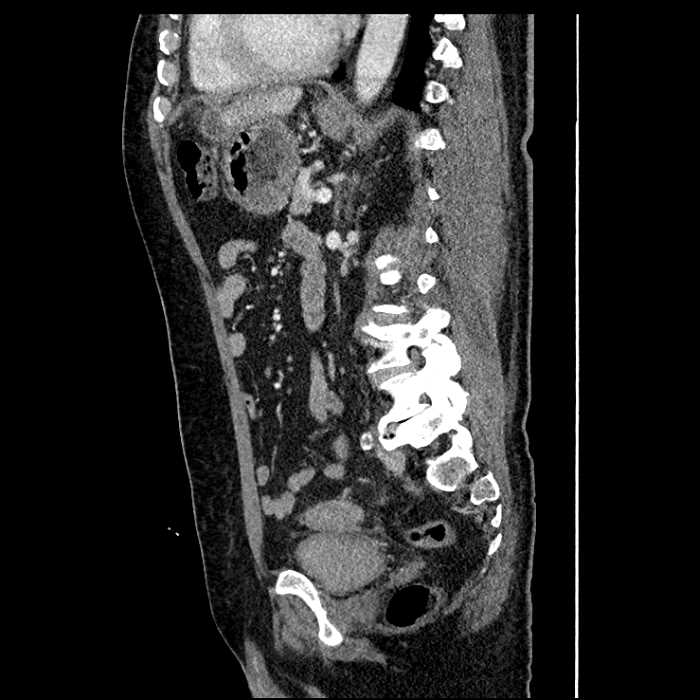

• Large fluid density structure in hepatic segments 7 and 8 measuring 10 x 7 x 7 cm with internal septation and circumferential ill-defined low density compatible with edema

• Peripherally enhancing subcapsular collections along the anterior margin of the left hepatic lobe measuring 3 x 1 cm and 2 x 1 cm

• Clearly marginated fluid density structure in segment 7 and several other scattered tiny hypodensities, which likely represent cysts

Acute sigmoid diverticulitis complicated by a small contained perforation and a large abscess in the right hepatic lobe. Additional small subcapsular abscesses along the anterior margin of the left hepatic lobe.

• The classic CT imaging appearance is a double target sign with internal low density surrounded by an internal enhancing rim (capsule) and a low density external rim (edema)

Hepatic abscess showing the double target sign with low density internally surrounded by a thin inner enhancing rim (red arrow) and ill-defined outer low density rim (yellow arrow). Blue arrow indicates an internal septation. Red arrows: additional smaller subcapsular abscesses. Red arrow: focal contained perforation associated with diverticulitis.